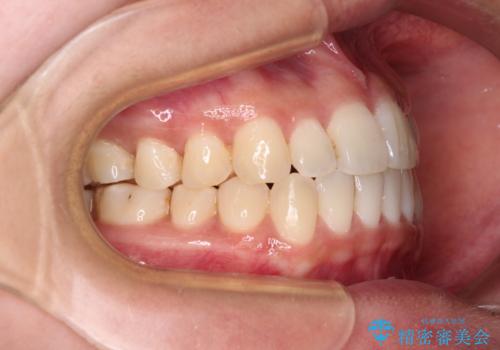

すきっ歯とオープンバイトをインビザラインで改善

- 前歯の上下スペースと前歯の隙間を気にして来院された患者様です。

インビザラインにより上下の前歯の隙間を閉じていくこととしました。

上下の隙間に舌が入り込むことが、すきっ歯やオープンバイトの原因であったため、舌の筋肉のトレーニングも並行して行い、後戻りの抑制を図りました。